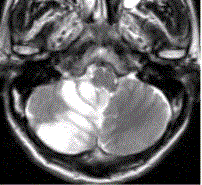

问题 患者女,75岁,突发偏瘫、头痛、头晕10h。既往有高血脂、糖尿病史。MRI表现如下图。 初步诊断为

选项 A.脑星形细胞瘤 B.脑急性血肿 C.蛛网膜下隙出血 D.脑急性梗死 E.急性化脓性脑炎

答案 D